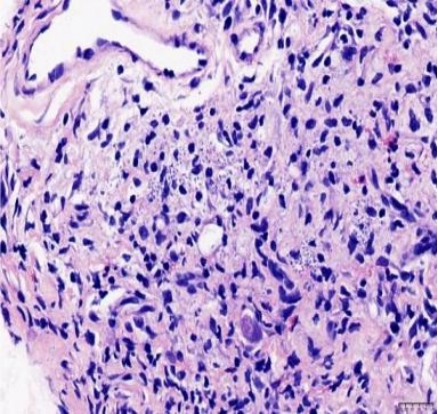

摘要:目的 探讨获得性免疫缺陷综合征(AIDS)合并马尔尼菲篮状菌(TM)感染导致肠道感染的内镜下特征。方法 回顾性分析2022年11月-2024年10月于该院确诊为AIDS合并TM感染导致肠道感染的6例患者的临床资料。包括:临床症状、实验室检查、影像学检查、内镜检查和病理检查等。结果 6例患者中,男5例,女1例;发病年龄26~67岁;AIDS合并TM感染导致肠道感染患者的临床表现为:腹泻、腹痛、腹胀和恶心呕吐。其中,2例有消化道出血表现。实验室检查:6例患者外周血白细胞计数为(1.37~4.49)×109/L,血红蛋白计数为(67~99)g/L;CD4+T淋巴细胞为(1~52)个/μL,CD8+ T淋巴细胞为(61~321)个/μL,CD4+T淋巴细胞/CD8+T淋巴细胞比值为(0.01~0.18)。6例患者均行HIV RNA检测。其中,5例HIV RNA阳性。血培养:可见丝状真菌,报告显示为TM。影像学检查:6例患者CT结果可见肠系膜及腹膜后多发淋巴结肿大。内镜检查:6例患者内镜下均可见肠道病变。其中,十二指肠糜烂溃疡2例,结肠多发糜烂溃疡4例。病理检查:6例患者幽门螺杆菌(Hp)结果均为阴性,黏膜下可见成簇的小球形真菌孢子,符合TM感染;特殊染色:PAS(+),六胺银染色(+)。结论 当AIDS晚期患者出现消化道症状时,应警惕TM感染,病变部位常见于全结肠和直肠,亦可累及十二指肠,内镜下表现多为溃疡、糜烂和隆起性病变,形态表现无特异性;及时行胃肠镜检查、病理活检、特殊染色和免疫组化是确诊的关键。